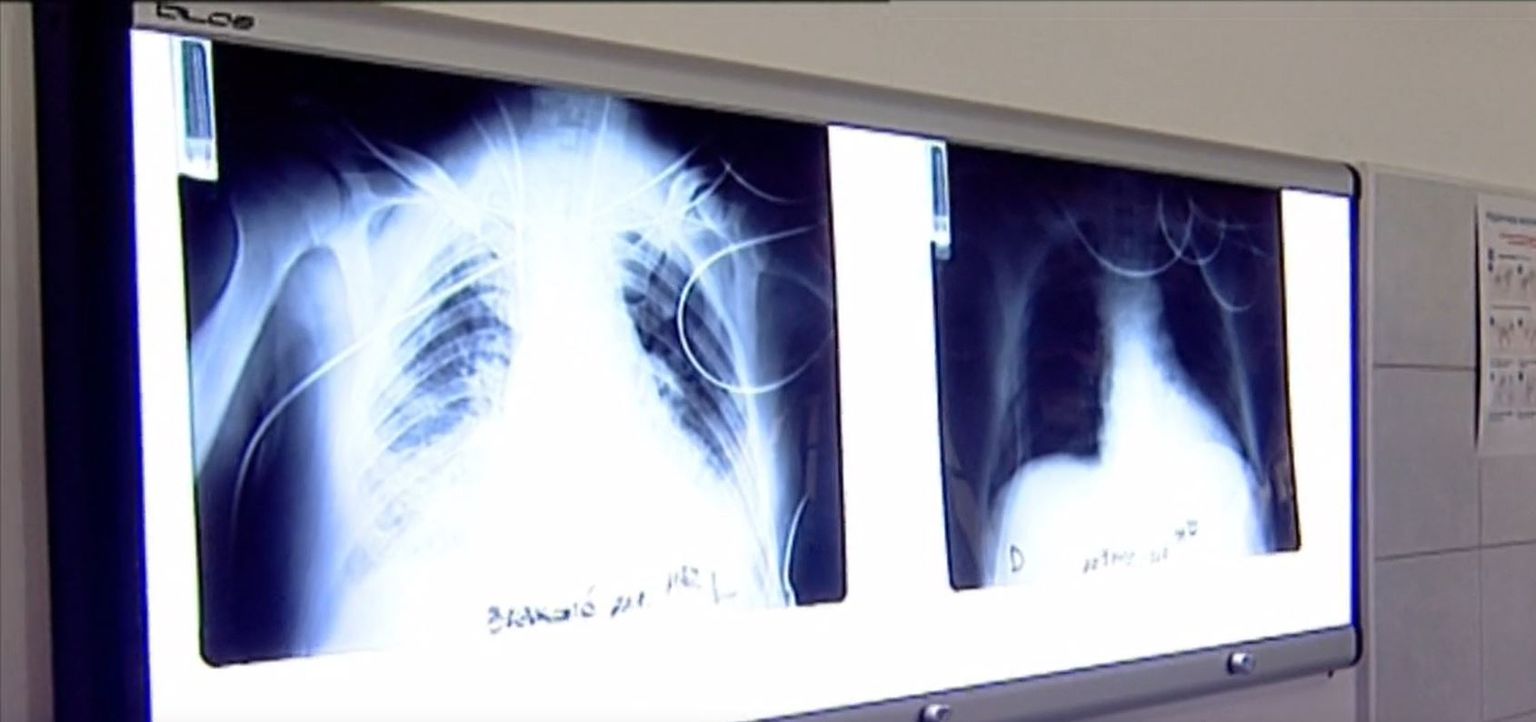

• Štrajk u bolnicama - 1 Foto: DNEVNIK.hr

• Štrajk u bolnicama - 2 Foto: DNEVNIK.hr

• Štrajk u bolnicama - 3 Foto: DNEVNIK.hr

• Štrajk u bolnicama - 4 Foto: DNEVNIK.hr